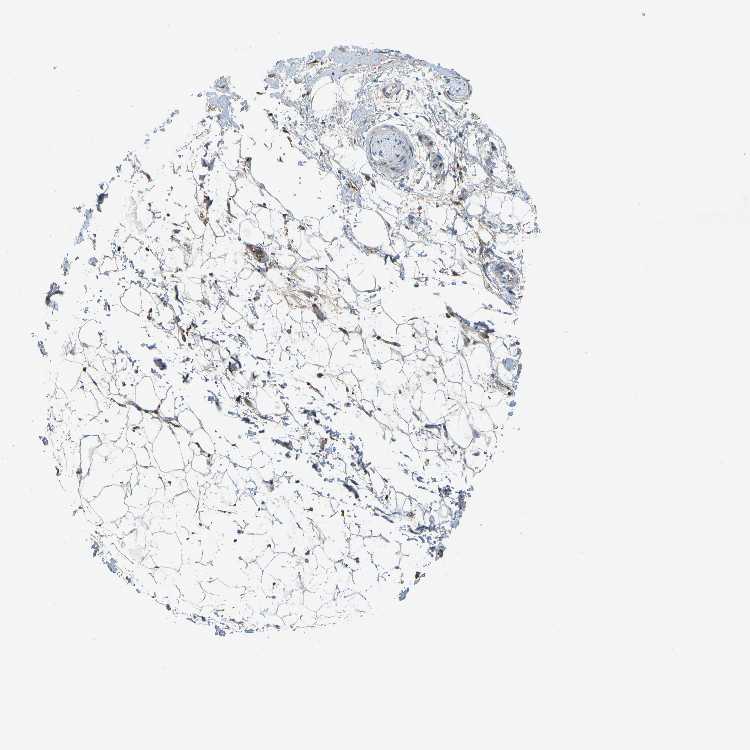

SOFT TISSUE 1 - Antibody stainingi

Antibody staining in the annotated cell types in the current human tissue is reported as not detected, low, medium, or high, based on conventional immunohistochemistry profiling in selected tissues. This score is based on the combination of the staining intensity and fraction of stained cells.

Each image is clickable and will lead to virtual microscopy that enables deeper exploration of all samples and also displays staining intensity scores, fraction scores and subcellular localization as well as patient and tissue information for each sample.

Antibody CAB004597

Fibroblasts Low

Peripheral nerve Not detected

SOFT TISSUE 2 - Antibody stainingi

Peripheral nerve Low